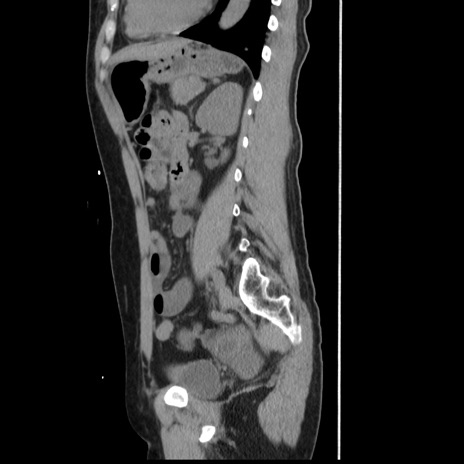

症例10(矢状断像)

【症例】 50歳代女性

【主訴】 腹痛

【現病歴】前日生レバーを食べた。今朝に排便あり。 昼前に突然発症の腹痛を生じ、当院救急外来を受診した。

【既往歴】 子宮筋腫にてで子宮全摘後

【身体所見】 意識清明、腹部:平坦、軟、下腹部やや左を中心に圧痛・反跳痛あり、筋性防御あり

【データ】WBC 7800、CRP 0.07